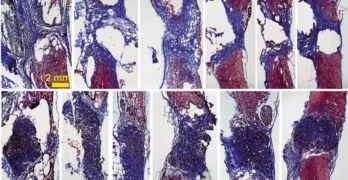

Científicos de Parapléjicos lideran un estudio que abre nuevas vías para entender la muerte de neuronas tras lesión medular

El trabajo ha sido publicado en la revista científica International Journal of Molecular Sciences